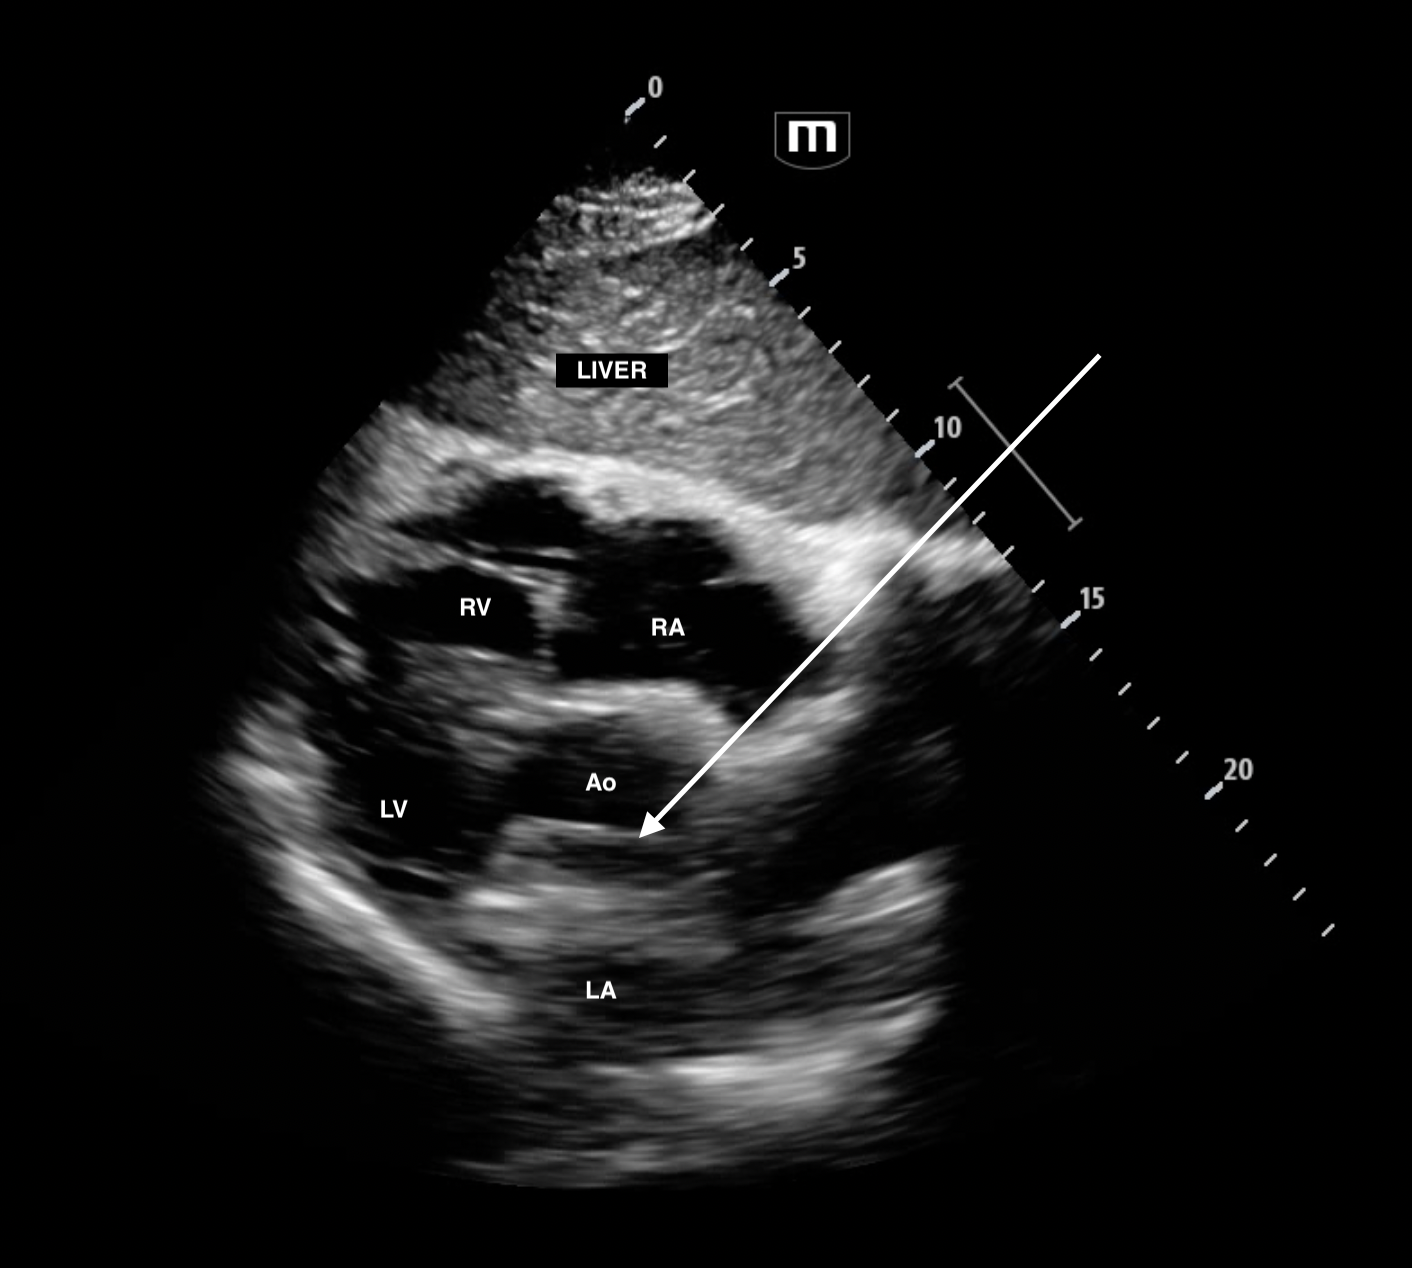

subxyphoid 5 chamber view (ie transducer fanning anteriorly to reveal aorta)

Still of the subxyphoid from above with arrow pointing to dissection flap.